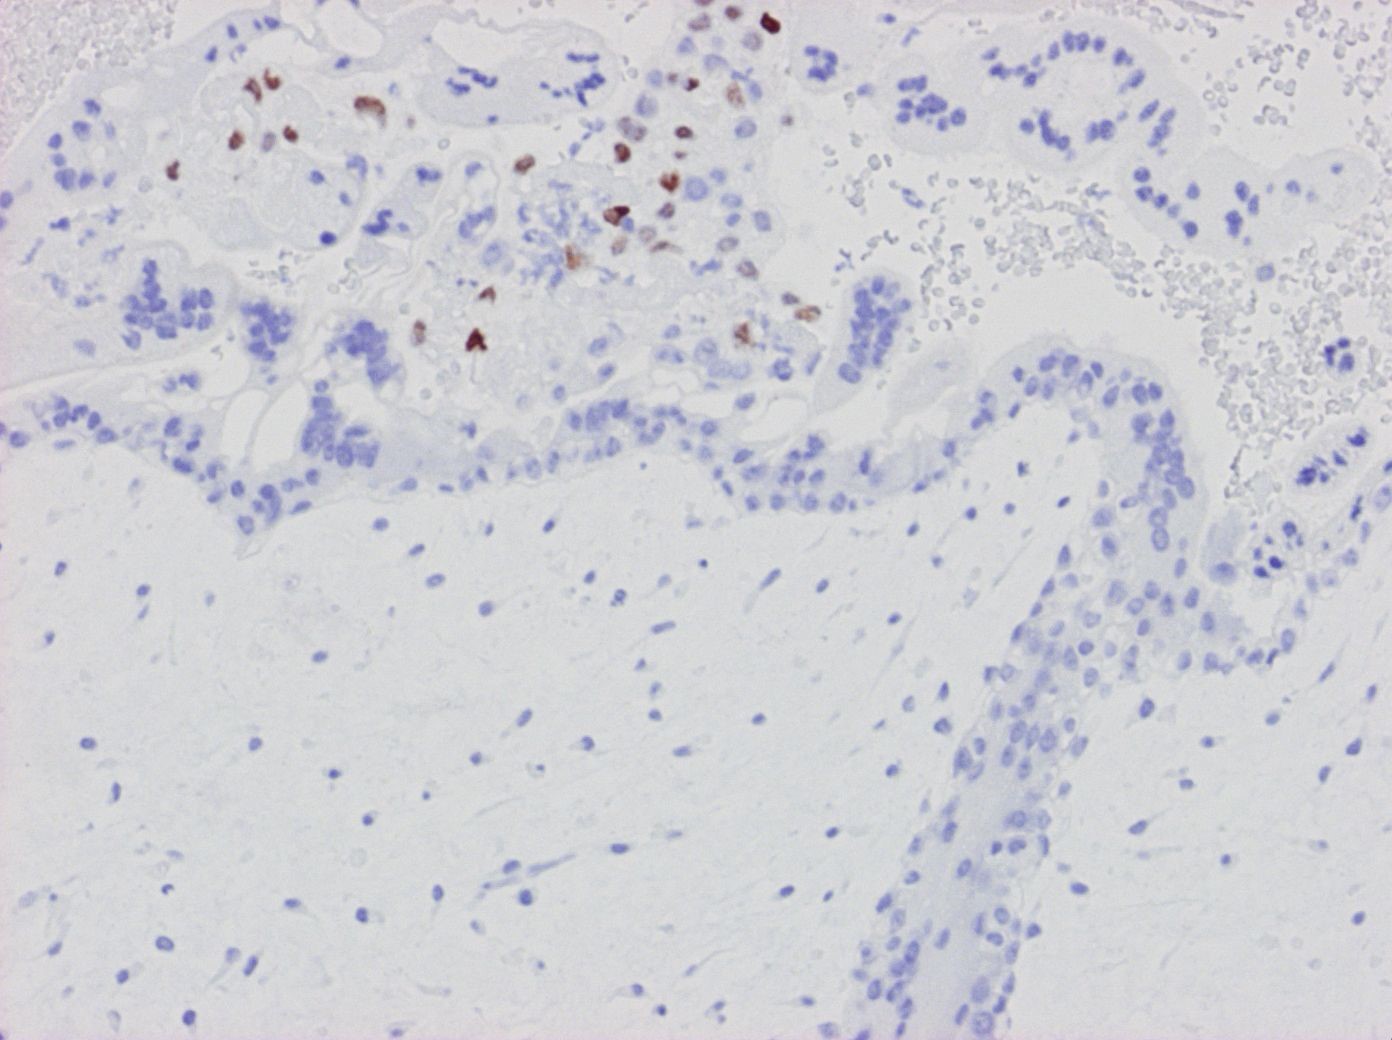

Eftersom immunhistokemisk färgning för cellcykelinhibitorn och tumörsuppressorn P57KIP2 (känd sedan millennieskiftet) är underuttryckt i cytotrofoblaster och stromala celler i villi som endast innehåller paternellt genom (kompletta molor), kan denna färgning hjälpa till att skilja kompletta molor från partiella molor och hydropa aborter vilka båda har biparental kromosomuppsättning. Infärgning i villis yttersta cellager med syncytiotrofoblaster är dock alltid negativt medan implantationstrofoblaster, intervillösa trofoblastproliferationer och decidua alltid är infärgade och fungerar som positiva interna kontroller 124127128.

Figur 7. Komplett mola p57KIP